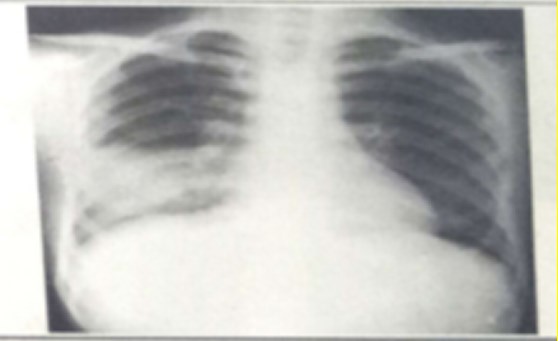

試題:男性,26歲,受涼后寒顫高熱,咳嗽,咳鐵銹色痰5天(2分)

A.肺癌

B.氣胸

C.正常胸片

D.肺炎

答案:D